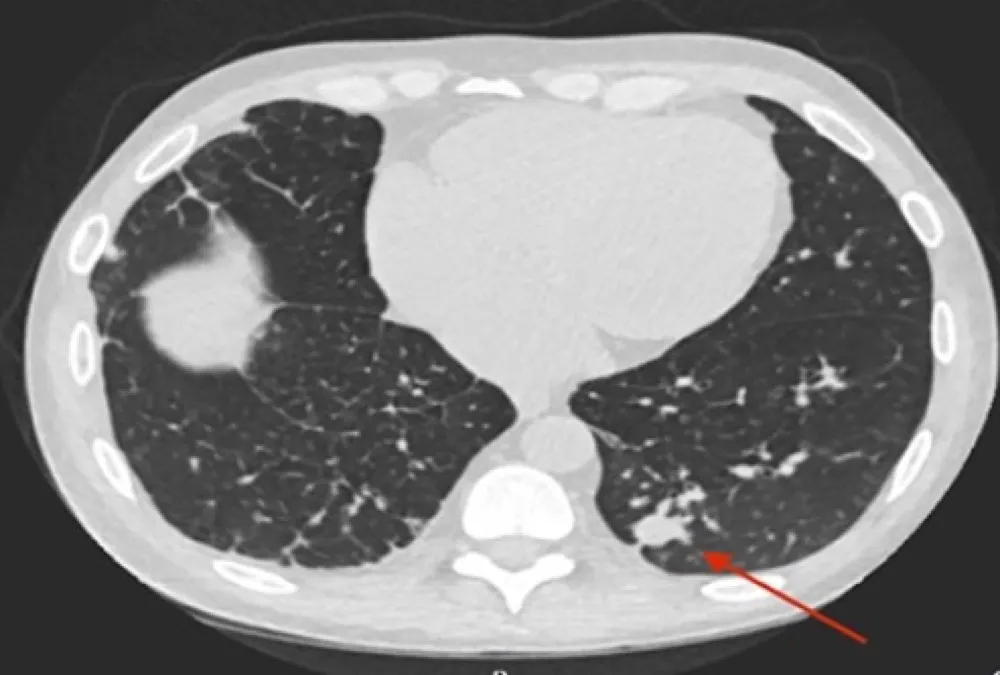

Uma causa incomum de hematúria glomerular intermitente!

Hematúria pós infecção, caso clínicos para auxiliar no entendimento de causas glomerulares comuns e raras...